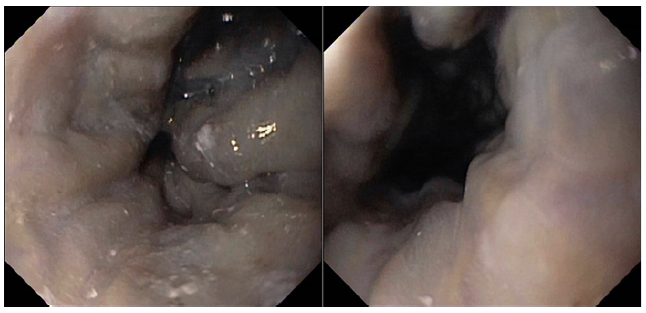

Coronary angiography ruled out coronary disease. Thoraco-abdominal computed tomography angiography showed enlarge-ment of the pulmonary artery with no evidence of thrombus, as well as absence of porto-systemic collateralizaion, portal vein thrombosis, and structural lung disease. A re-evaluation endos-copy showed large but reduced esophageal varices, without red spots (shown in Fig. 2).

Fig. 2. Large esophageal varices, reduced in size in comparison to the previous eval-uation, without red spots.